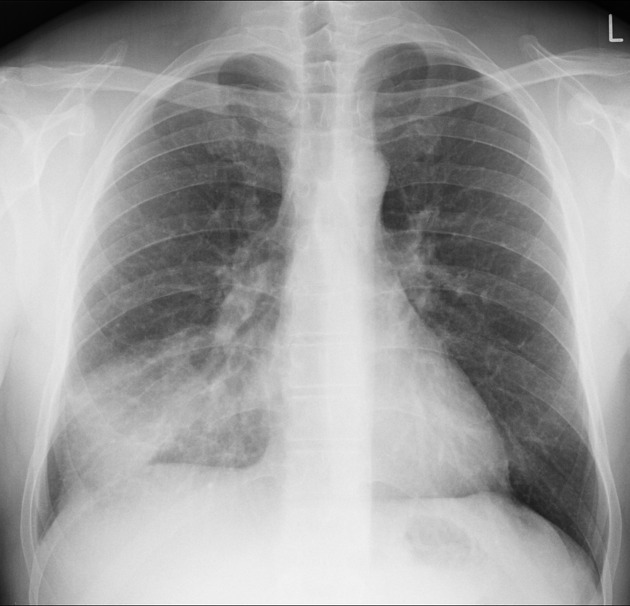

What is the gold standard imaging technique for suspected pneumonia?

What might you see?

CXR is the gold standard

Unilateral - consolidation, typically in the lower lobes.

Air bronchograms? - dilated bronchi

What is the difference between a LRTI and pneumonia?

Pneumonia shows consolidation on a CXR alongside symptoms of a LRTI If not CXR findings than just a LRTI

What is the terminal result of pahtophysiology that underpins pneumonia, including causing CXR changes?

Terminal alveoli and lung tissues become filled with infective material.